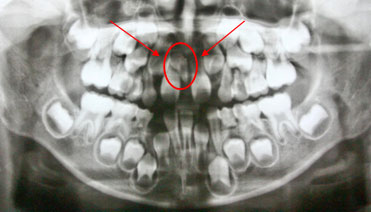

*This is a panoramic x–ray of a six–year old patient with an extra inverted tooth which was surgically removed to close the gap of the incisor.